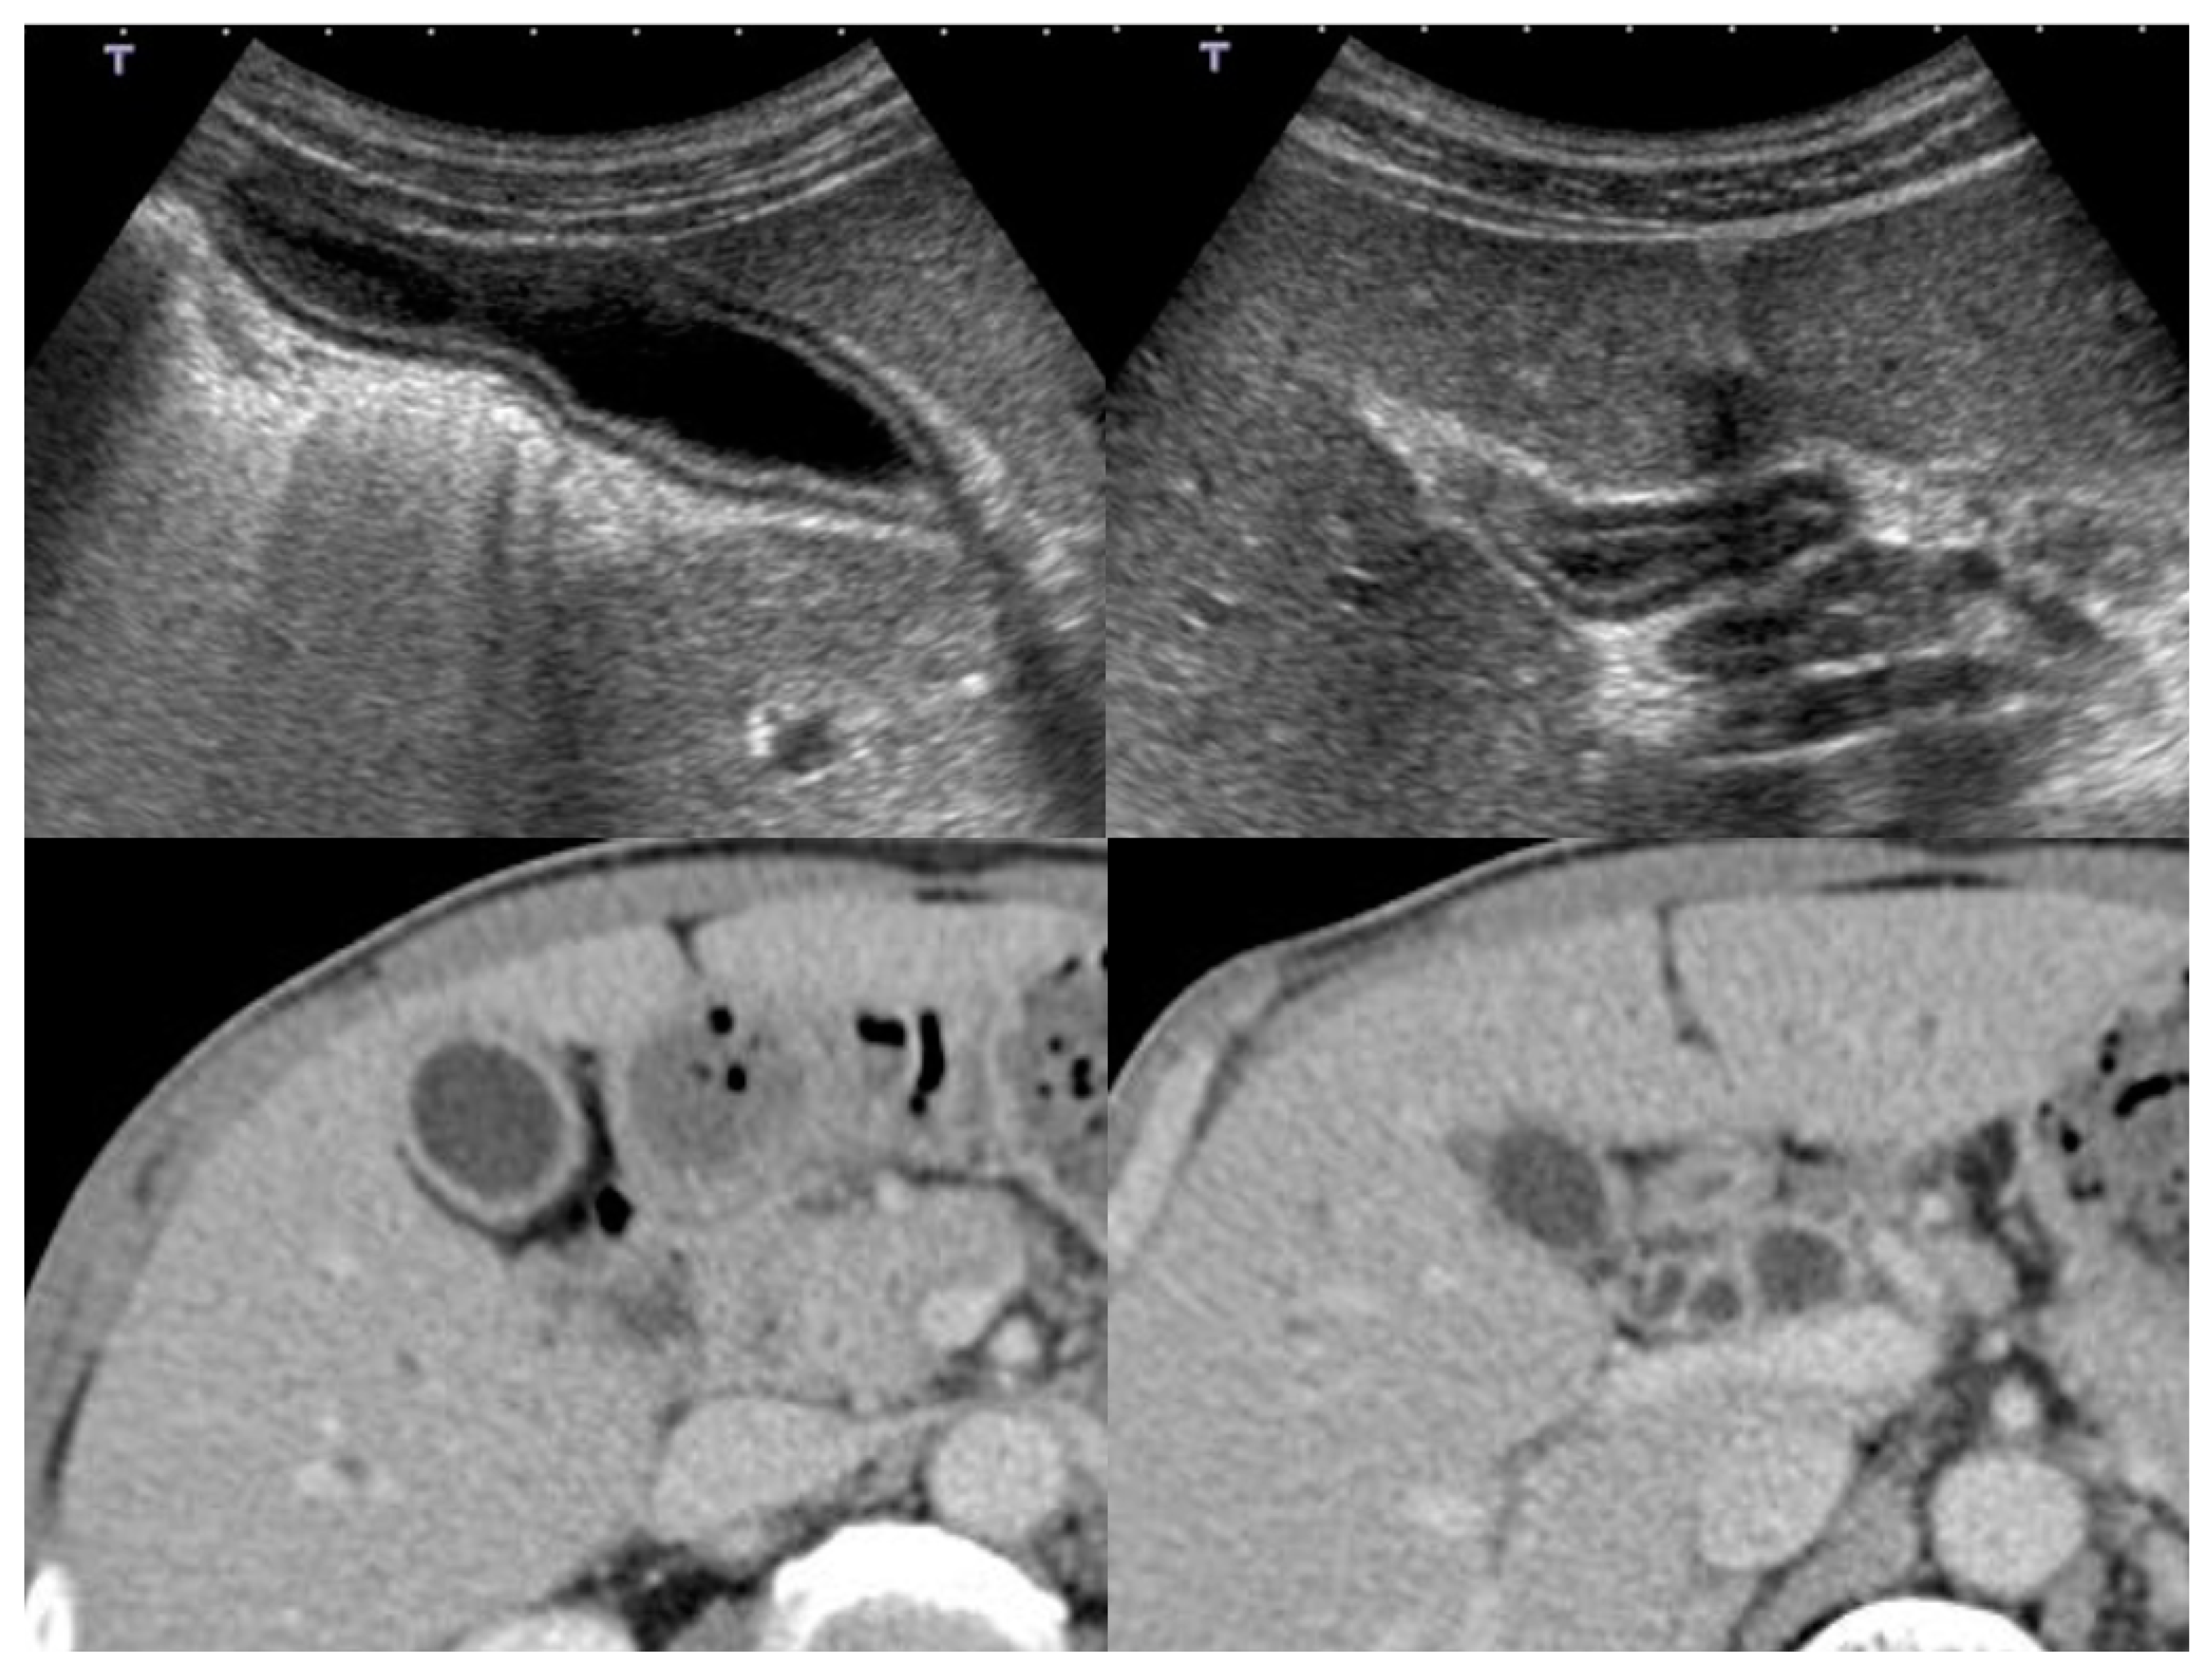

5.2. Adenomyomatosis

5.3. Xanthogranulomatous Cholecystitis (Chronic Cholecystitis)

5.4. Malignant Lymphoma

5.5. Metastatic Neoplasm